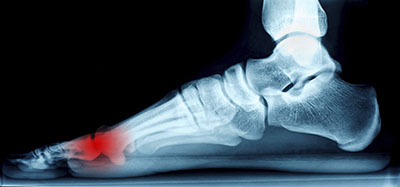

The pain caused by Morton’s neuroma is typically experienced at the ball of the foot. Many have described the sensation as feeling like they have a pebble stuck in their shoe. Because of this, those with the condition may find walking to be more difficult and uncomfortable. They may also experience a numbing or burning sensation in the foot. One of the most common factors that influence the development of Morton’s neuroma is improper footwear. Those who generally wear tightly fitted shoes or shoes with higher heels are more at risk at getting Morton’s neuroma. Having a foot abnormality may also increase the risk of getting this condition, as it may cause instability, thus adding more pressure onto the nerves of the foot. Certain foot conditions such as bunions, hammertoes, and flat flat feet have also been known to lead to Morton’s neuroma if not treated promptly.

Athletes have a tendency of getting Morton’s neuroma due to repetitive motions and pressure placed on the ball of the foot while running or jumping. Morton’s neuroma may also develop as a result of an injury to the foot.